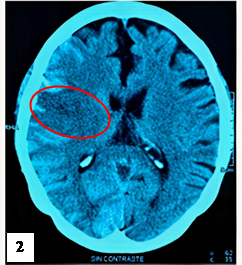

A las 3h, la escala NIHSS fue de 19 puntos, asociada a hemiplejía izquierda, lateralización de la mirada a la derecha y compromiso severo de conciencia. Se indicó una TEM cerebral sin contraste control, encontrándose foco isquémico en región parietal derecha, asociado a hemorragia subaracnoidea (figura 2). Luego de permanecer 7 horas en emergencia, ingresa a UCI. A las 12 horas se registra PA de 181/85 mmHg, asociado a taquicardia, taquipnea y febrícula (37,6°C). A las 24h se realiza una TEM cerebral y una angio-TEM que reveló un ECV isquémico con transformación hemorrágica post trombólisis, sin presencia de aneurisma roto (figura 3). La paciente permaneció en UCI en ventilación mecánica. A los 10 días, se realizó una TEM control que reveló menor volumen de hematoma en comparación al estudio tomográfico previo (figura 4). A los 20 días tras su ingreso a UCI fue dada de alta.

Foco isquémico (círculo rojo) en parietal derecho de bordes definidos asociado a hemorragia subaracnoidea.